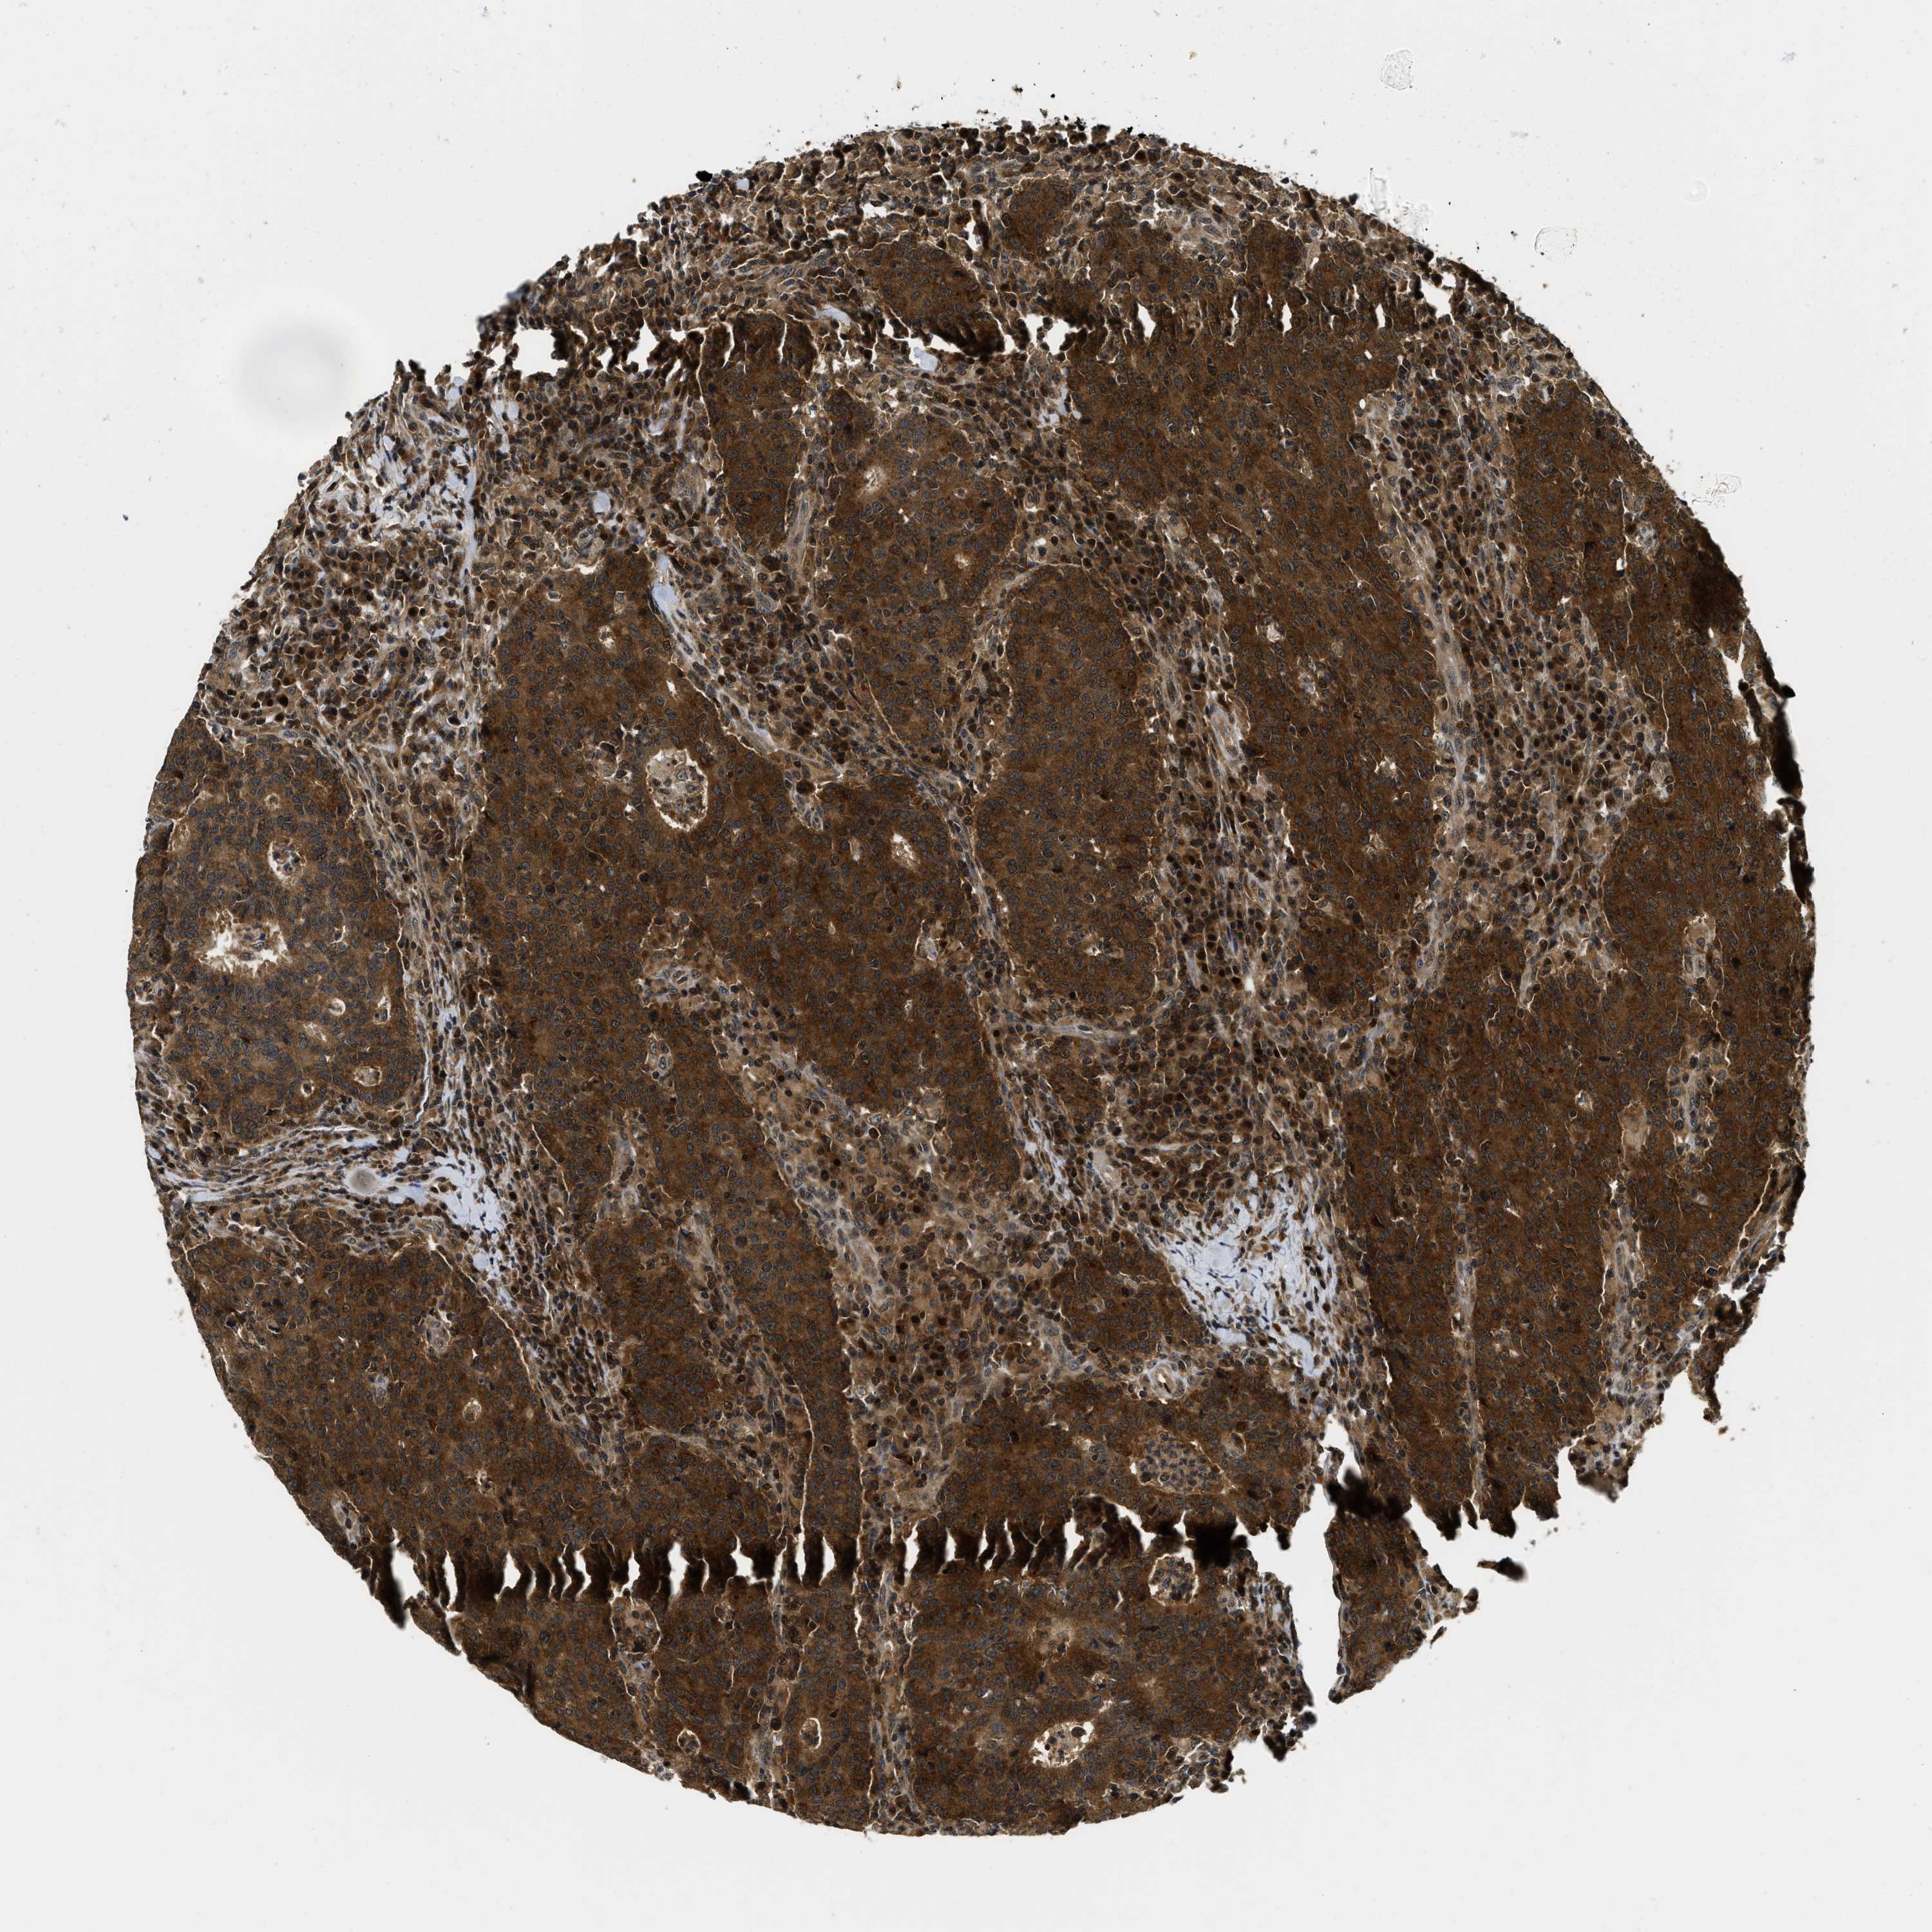

CANCER COLORECTAL CANCER Show tissue menu

ANTIBODIES

AND

VALIDATION